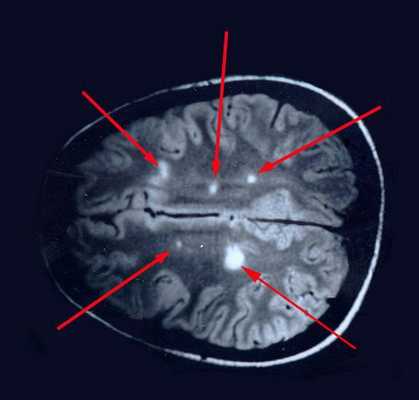

При вероятном РС, наряду с полным неврологическим осмотром, необходимо проводить исследование головного и спинного мозга при помощи МРТ. Этот способ исследования является наиболее информативным дополнительным методом диагностики. С его помощью можно обнаружить участки изменённой плотности в белом веществе головного мозга (очаги демиелинизации и глиоз). [10]

Рис. 1. Соотношение клинических и МРТ-проявлений активности РС.

Рис. 2, 3. Типичное расположение очагов РС на МР-томограммах.

Следующим шагом после клинического предположения о PC является магнитно-резонансная томография (МРТ) - метод выбора инструментальной диагностики PC. Это неинвазивное и безопасное исследование позволяет визуализировать патологические очаги в центральном нервной системе, демонстрируя необходимую для диагностики диссеминацию процесса в пространстве (многоочаговость) и во времени (очаги "разного возраста", а также исследование в диамике). Это наиболее информативный инструментальный метод диагностики PC. Его чувствительность при разных формах PC -85-95%. Однако общепринятые МРТ-критерии PC (табл. 3) следует использовать лишь в качестве базисных. Разработаны дополнительные МРТ-характеристики, которые повышают специфичность метода. Они включают определенные варианты локализации и ориентации очагов, особенности проявлений отека вещества мозга и накопления контраста, а также изменения, наблюдаемые в динамике.